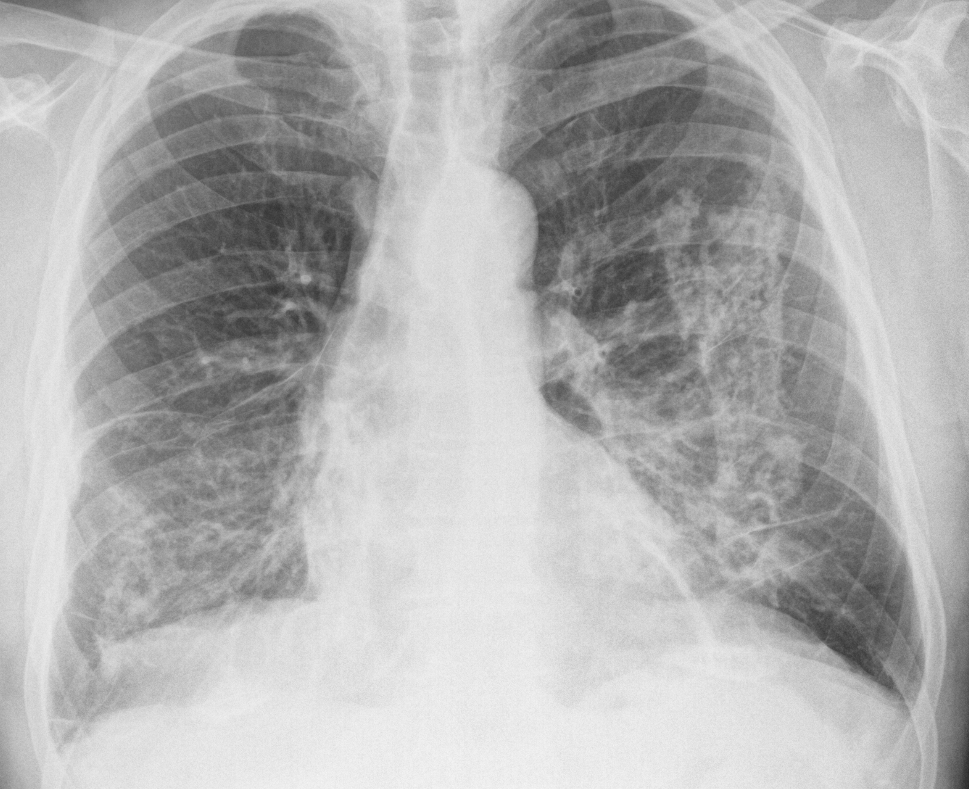

Уплотнение корней — один из наиболее часто встречающихся рентгенологических синдромов, который врач-рентгенолог определяет на обзорной рентгенографии грудной полости. Что это означает: «уплотнены корни легких»? Какие заболевания и патологические состояния скрываются под этой фразой?

Корень легкого: что это такое?

Корень легкого — это комплекс структур, расположенных в воротах легкого. К ним относятся легочная артерия, вена, главный бронх, а также нервы, лимфатические сосуды, плевра, жировая клетчатка. Все эти структуры расположены в строго определенном порядке, однако часть их с левой стороны не видна на рентгенограмме, скрываясь за тенью сердца.

На обзорной рентгенографии и флюорографии под таким понятием, как корень легкого, подразумевают только крупные сосуды (артерию, вену) и бронх.

Основные характеристики корней легких

Чтобы определить на рентгене такой симптом, как уплотнение корней легких, в первую очередь нужно знать особенности этих образований в норме.

Корень как правого, так и левого легкого состоит из трех частей: головки, тела и хвоста. В состав хвоста входят конечные мелкие разветвления сосудов.

В рентгенологии также определяют ширину данных структур. Определяется она обычно по ширине правого корня и включает в себя артерии и промежуточный бронх. В норме его ширина составляет 1,5-2 см.

Стоит также отметить, что артерии в корнях легкого расположены более вертикально, а вены — горизонтально. Иногда их структура может быть неоднородной из-за того, что на некоторых участках видны просветления воздуха в бронхах.